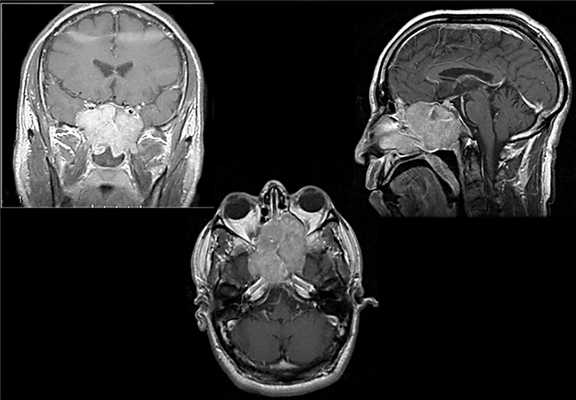

При КТ головного мозга преимущественно в левой лобно-височно-теменной области определяется крупное объемное образование с достаточно четкими бугристыми контурами размером 78×76×64 мм, в базальных отделах прорастающее в правую лобную долю на 10-12 мм. Образование интимно прилежит к сифону левой ВАС, дну передней черепной ямки и к переднему бугорку турецкого седла, кости, образующие дно передней черепной ямки, «изъедены». Образование компримирует передние отделы левого бокового желудочка и, вероятно, распространяется в его просвет. При внутривенном контрастном усилении образование несколько неравномерно накапливает контрастный препарат (до +60 - +85 Ед. Хаунсфильда). К образованию подходит множество артериальных сосудов диаметром до 2-3 мм, преимущественно с медиальной и передней сторон образования. Определяется незначительно выраженный перифокальный отек (максимально до 7 мм у латерального края образования в левой височной области) (рис. 2).

Рисунок 2. КТ с контрастным усилением до операции. а - аксиальная проекция; б - фронтальная проекция. В левой лобно-височно-теменной области определяется крупное объемное образование с достаточно четкими бугристыми контурами размером 78×76×64 мм, в базальных отделах прорастающее в правую лобную долю на 10-12 мм. Образование компримирует передние отделы левого бокового желудочка и, вероятно, распространяется в его просвет, образование неравномерно накапливает контрастный препарат. Определяется незначительно выраженный перифокальный отек.

КТ с контрастным усилением в 1-е сутки после операции не выявила участков патологического накопления контраста. Опухоль удалена радикально (рис. 4).

Рисунок 4. КТ с контрастным усилением. 1-е сутки после операции. а - аксиальная проекция; б - фронтальная проекция. Опухоль удалена радикально, геморрагических осложнений в ложе удаленной опухоли нет.

При контрольных КТ и МРТ с контрастным усилением через 5 мес после операции нет признаков рецидива (рис. 5).

Рисунок 5. КТ с контрастным усилением в аксиальной проекции (а) и МРТ с контрастным усилением в аксиальной (б) и фронтальной (в) проекциях. 5 мес после операции (признаков рецидива опухоли нет).